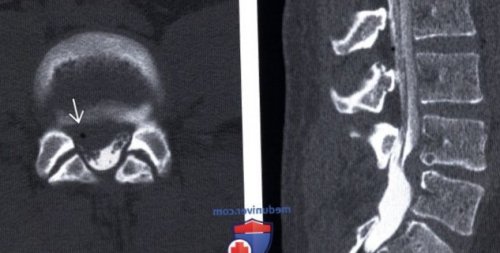

(Слева) КТ, аксиальный срез: на уровне L5-S1 отмечается частичная о Уменьшение содержания (Справа) Т2-ВИ, сагиттальный срез: крупная экструзия диска

влево. Небольшой фокус газа уровня, смежного с уровнем сдавлением корешка и

кальцификация умеренного размера

L2-L3. Обратите внимание на